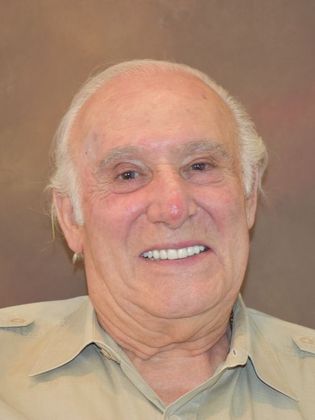

Prettau Zirconia Implant Bridge: Louis

Description

As an artist, Louis has a keen eye for detail. It especially bothered him to look in mirror and see the detail of missing teeth. Getting a compliment from him on the artistry of the new teeth is a remarkably rewarding